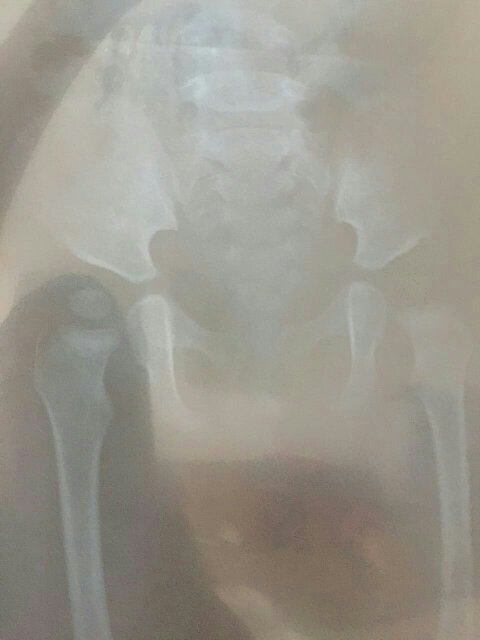

十个月婴儿髋关节骨骨化中心左侧明显小于右侧,双髋关节完整双侧骨骨化中心均在髋臼内左侧髋臼边缘不规则软组织清晰,臀纹不对称,请问什么原因骨骨化中心一侧大一侧小?是先天性髋关节脱位吗?还是缺钙?或是长期挤压造成?怎样治疗?